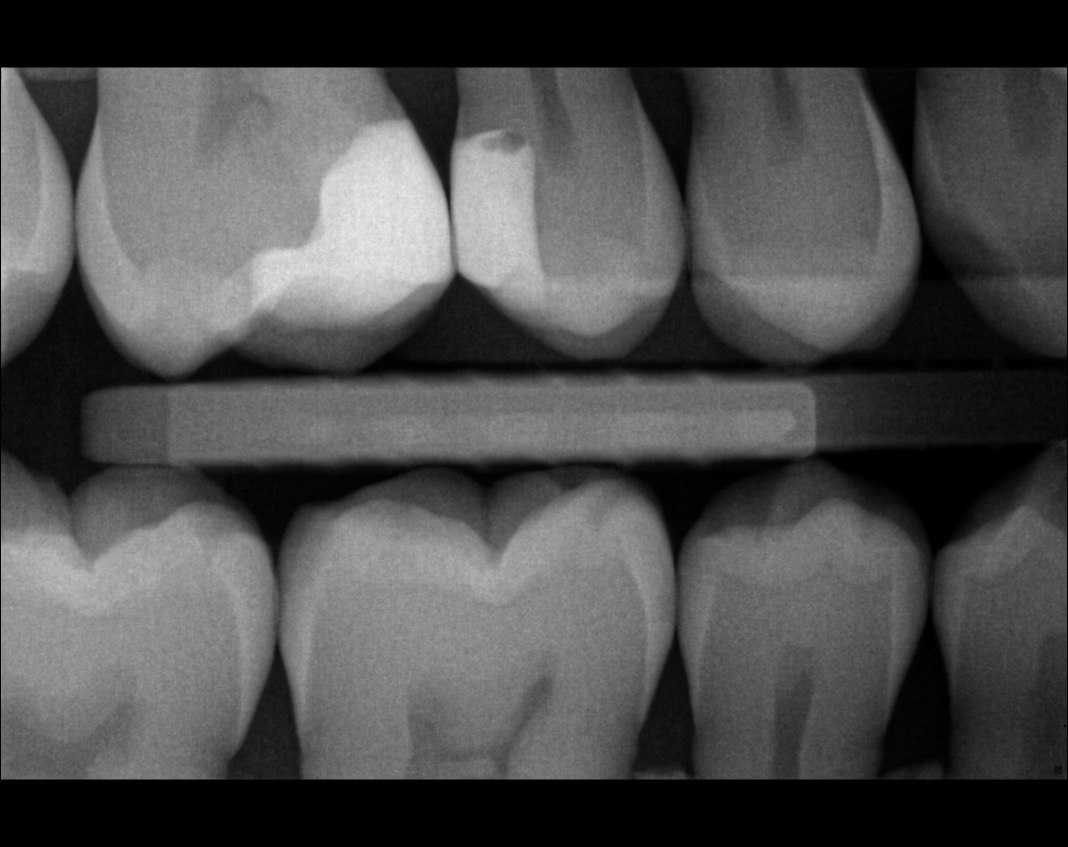

Quistion 11: What are the conditions of the distal and mesial surfaces of the tooth # 4.5 respectively?

Question 12: What option can describe the mesial surface of the tooth # 3.7?

Question 13: What option can describe the mesial surface of the tooth # 3.8?

Question 14: What option can describe the mesial surface of the tooth # 3.4?

Question 15: What option can be selected for treatment of the caries in mesial surface of the tooth # 3.4?